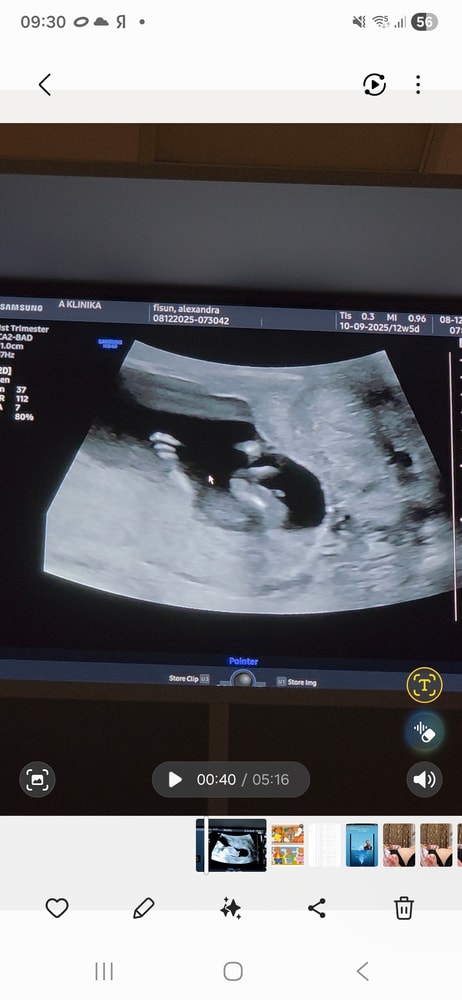

Мальчик или девочка УЗИ 12 недель

Половой бугорок смотрит вниз - девочка)

Ами, ну вот она и у мальчиков и у девочек торчит на таком сроке, только как бы по-разному))

Александра Тарталетка, половой бугорок лежит горизонтально, девочка . Я тоже скриншоты делала , у меня мальчик) Изображение

Больше на мальчика конечно похоже ))))но точнее скажут позже )

Александра , сказали ножки скрещивает, не посмотреть) а это я скриншоты из видео сделала, потому что прям чтобы посмотреть не сбоку, а между ног действительно не получилось, только сбоку кадры)

Александра Тарталетка, по УЗИ можно предположить мальчика но это так же могут быть и половые губы как я читала они у девочек набухшие изначально поэтому по узи точно тут не скажешь )